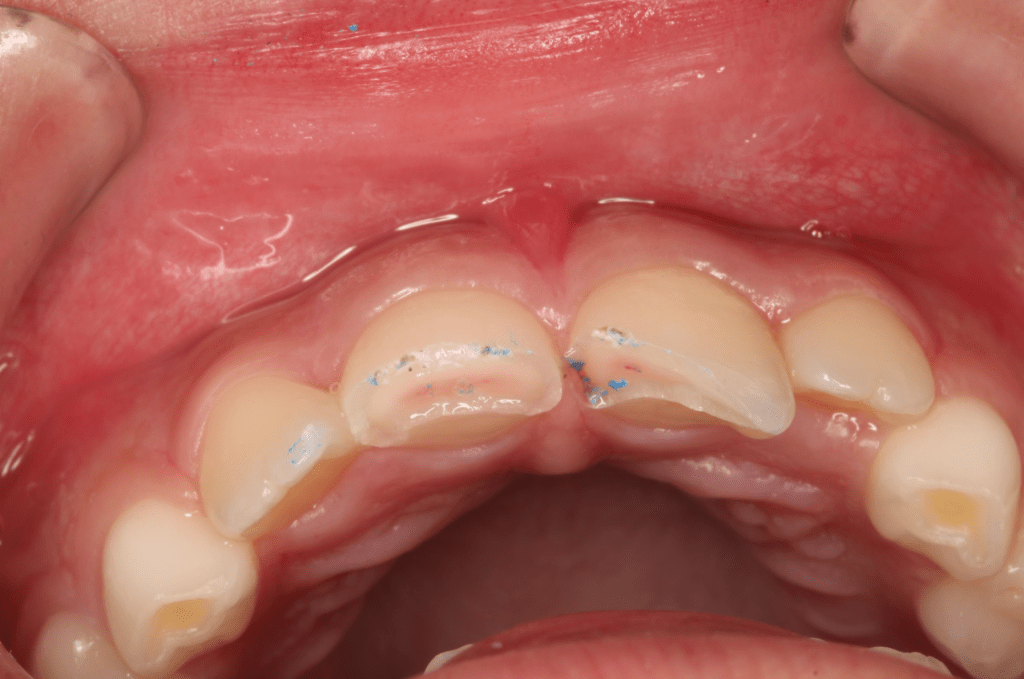

Fractura con exposición pulgar

Reconstrucción con recubrimiento pulgar indirecto